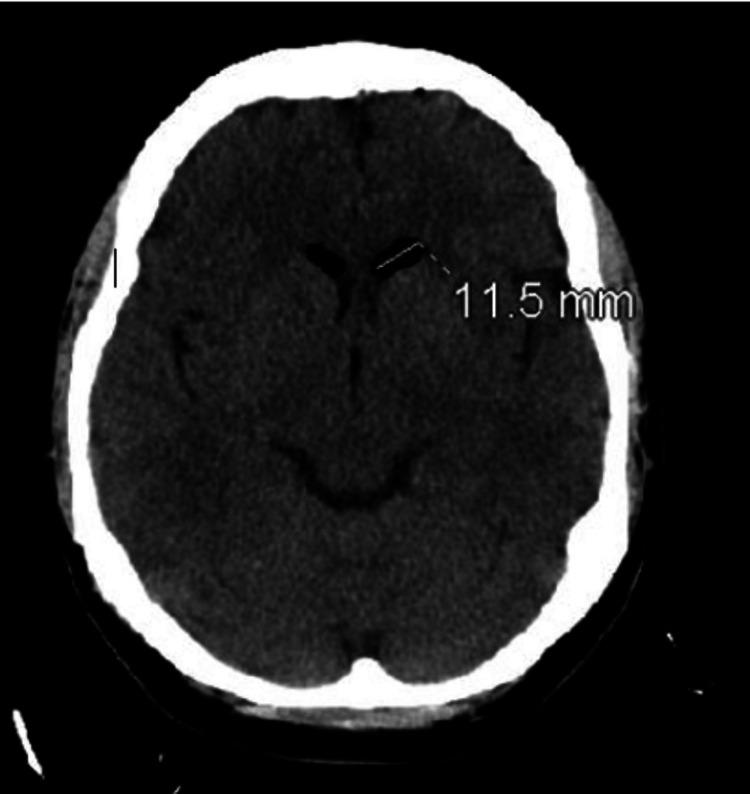

Pneumocephalus is a rare but potentially serious complication of spinal procedures, characterized by the presence of intracranial air. This report presents the case of a 40-year-old female who developed pneumocephalus following a lumbar epidural steroid injection. She presented to the emergency department with a persistent headache, blurred vision, and eye pain, which began shortly after the procedure. Computed tomography (CT) scans of the head and lumbar spine revealed several air pockets in the cerebellar cisterns and the left frontal horn, as well as in the epidural and paraspinal regions. Despite the presence of intracranial air, the patient's symptoms gradually improved with conservative management, including bed rest, caffeinated drinks, intravenous fluids, and symptomatic relief with butalbital-acetaminophen-caffeine. A repeat CT scan on day four showed a reduction in air pockets, and by day 10, all air pockets had resolved without the need for neurosurgical intervention. The patient's headaches subsided, though she experienced mild residual vision changes. This case emphasizes the importance of recognizing pneumocephalus as a potential complication of epidural steroid injections and highlights the efficacy of conservative treatment. While most cases of simple pneumocephalus resolve spontaneously, careful monitoring is essential to prevent progression to tension pneumocephalus, a life-threatening condition that requires urgent surgical intervention. Further studies are needed to evaluate the risks and outcomes of different techniques used during epidural procedures.

气颅是脊柱手术中一种罕见但可能严重的并发症,其特征为颅内存在气体。本报告介绍了一名40岁女性在接受腰椎硬膜外类固醇注射后发生气颅的病例。她在手术后不久因持续头痛、视力模糊和眼痛就诊于急诊科。头部和腰椎的计算机断层扫描(CT)显示小脑脑池和左额叶角以及硬膜外和椎旁区域有多个气腔。尽管存在颅内气体,但通过保守治疗,包括卧床休息、饮用含咖啡因饮料、静脉输液以及使用布他比妥-对乙酰氨基酚-咖啡因缓解症状,患者的症状逐渐改善。第四天的重复CT扫描显示气腔减少,到第十天时,所有气腔均已消失,无需神经外科干预。患者的头痛症状消退,不过仍有轻度视力残留改变。该病例强调了认识到气颅是硬膜外类固醇注射潜在并发症的重要性,并突出了保守治疗的有效性。虽然大多数单纯性气颅病例可自行缓解,但仔细监测对于预防进展为张力性气颅至关重要,张力性气颅是一种危及生命的情况,需要紧急手术干预。需要进一步研究来评估硬膜外手术中使用的不同技术的风险和结果。